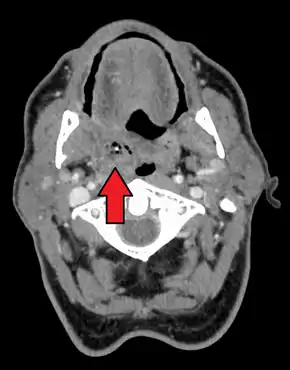

| Right sided peritonsillar abscess | |